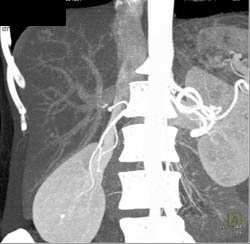

Focal Nodular Hyperplasia (FNH)